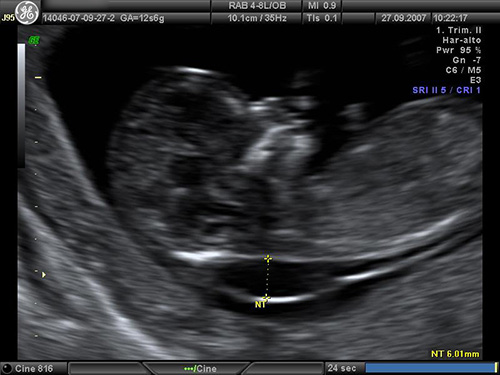

- un esame ecografico per misurare lo spessore di uno spazio compreso tra la cute e la colonna vertebrale dietro la nuca del feto (translucenza nucale)